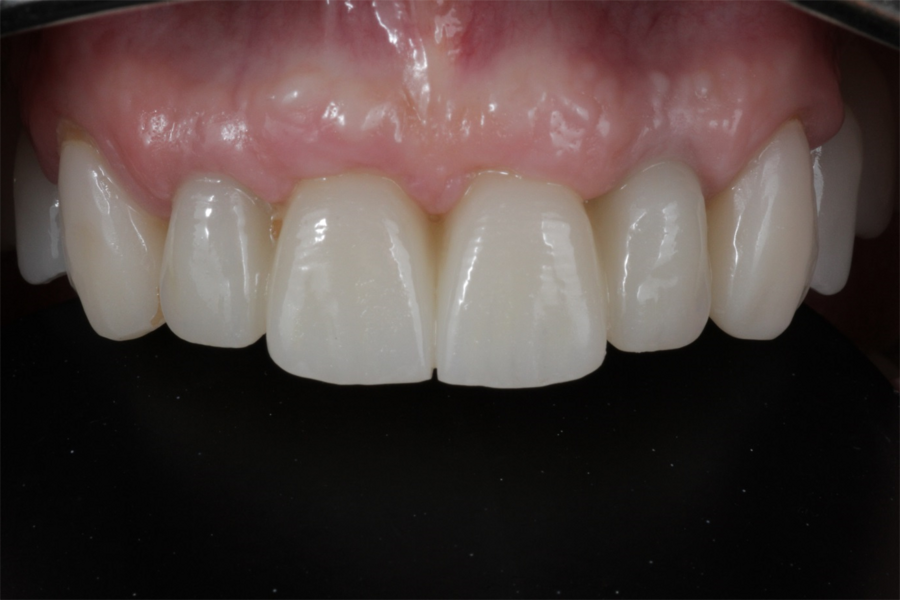

Definitive prosthetic treatment was performed after completion of implant healing with three CAD/CAM-fabricated monolithic zirconia bridges (DD cubeX2, Dental Direkt). The bridges were screwed on to BEGO titanium base abutments (Figs. 14–16). Good fit of the prosthetic superstructures was displayed in the radiograph after placement (Fig. 17). The two-year follow-up examination in July 2019 revealed excellent aesthetic and clinical soft-tissue conditions (Figs. 18–20). No radiographic bone loss had occurred at the implant sites (Fig. 21). Neither the submerged central incisors nor the distobuccal molar root displayed any signs of periapical inflammation, and the patient reported no complications. The patient’s oral hygiene had improved significantly during the follow-up period.

Fig. 14: Frontal aspect of the definitive prosthetic restorations, showing good aesthetic conditions with no signs of soft-tissue complications after insertion.